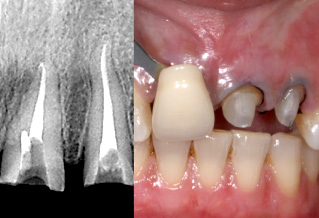

歯内療法、切除療法(FGG、歯肉強化)を行い、ファイバーコアを立てた後、適合の良いゴールドクラウンとオールセラミッククラウンを装着しております。